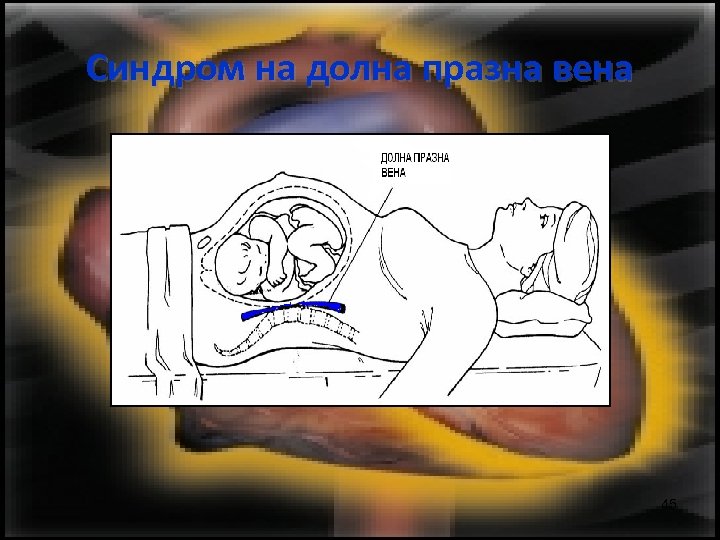

Синдром на долна празна вена Поради притискане на долната куха вена от плода е затруднено постъпването на кръв към сърцето. Необходима е спешна промяна в положението на бременната или родилката – поставянето й на ляво. 44

Синдром на долна празна вена 45